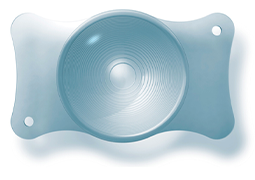

- Metric Causes of Refractive Errors of the Eye